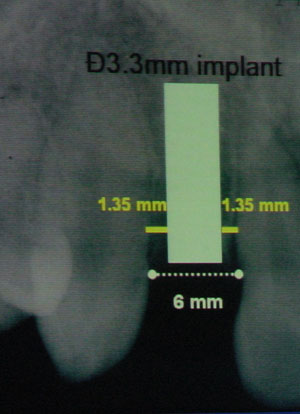

右の写真は右上の側切歯(前から2番目の歯)が無くなっているケースです。歯と歯との間の幅は6mmです。一番径の細いインプラントの幅は3.3mmです。そのため隣在歯を傷つけないようにするには、正確に中央にインプラントを埋入しなくてはなりません。左右のマージンはそれぞれ1.35mmしかありません。

右の写真は右上の側切歯(前から2番目の歯)が無くなっているケースです。歯と歯との間の幅は6mmです。一番径の細いインプラントの幅は3.3mmです。そのため隣在歯を傷つけないようにするには、正確に中央にインプラントを埋入しなくてはなりません。左右のマージンはそれぞれ1.35mmしかありません。

全くぶれることなくまっすぐに形成しないと、どちらかの歯の根を損傷する可能性があります。傾きが1度でも異なれば、事故を起こしてしまいます。

こういったケースでは、事故のおそれがあるので、インプラントは今までは薦められなかったでしょう。